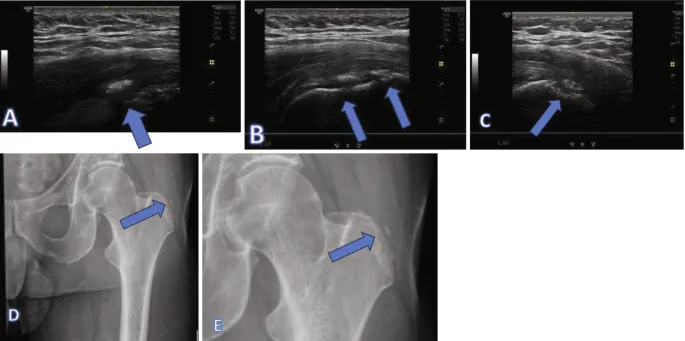

- Hip:

- Effusion/Synovitis: Anterior recess fluid/synovial thickening.

- Trochanteric Bursitis: Fluid/thickening.

- Gluteal Tendinopathy: Thickening/tears (medius/minimus).